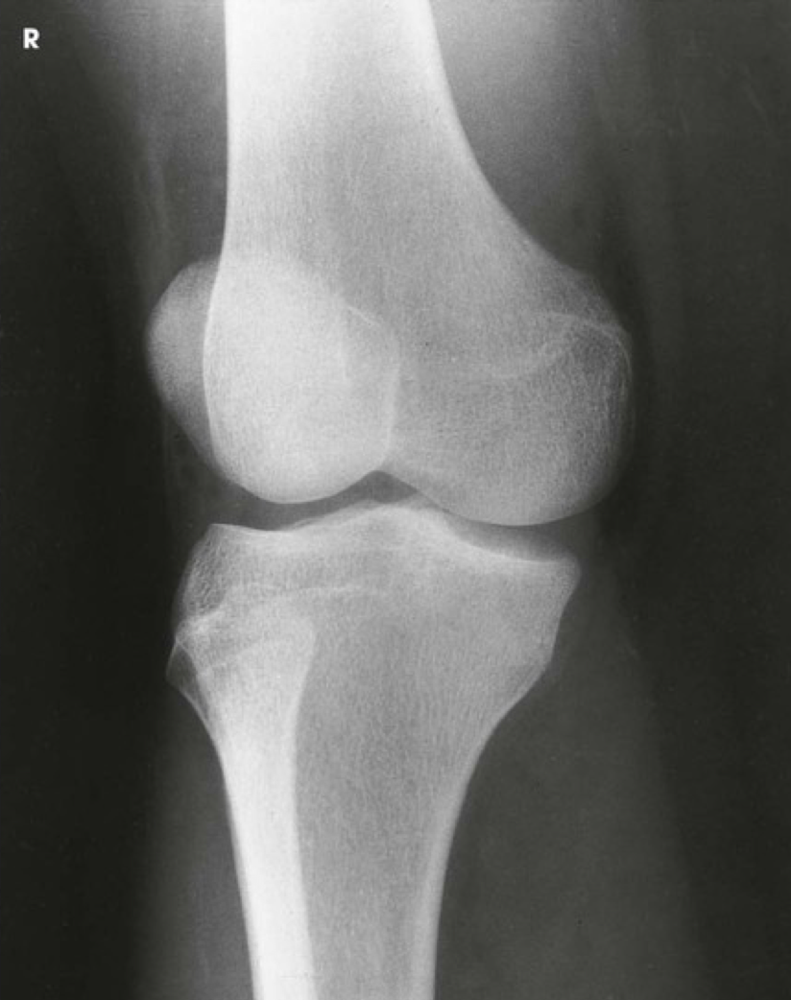

Question

Label the image

Image:

0e626c3f-6a7b-47c6-b350-8e3068a35b04 (image/png)

Answer

femur

patella

lateral epicondyle

lateral condyle

lateral tibial plateau

intercondylar eminence

head of fibula

tibia

fibula